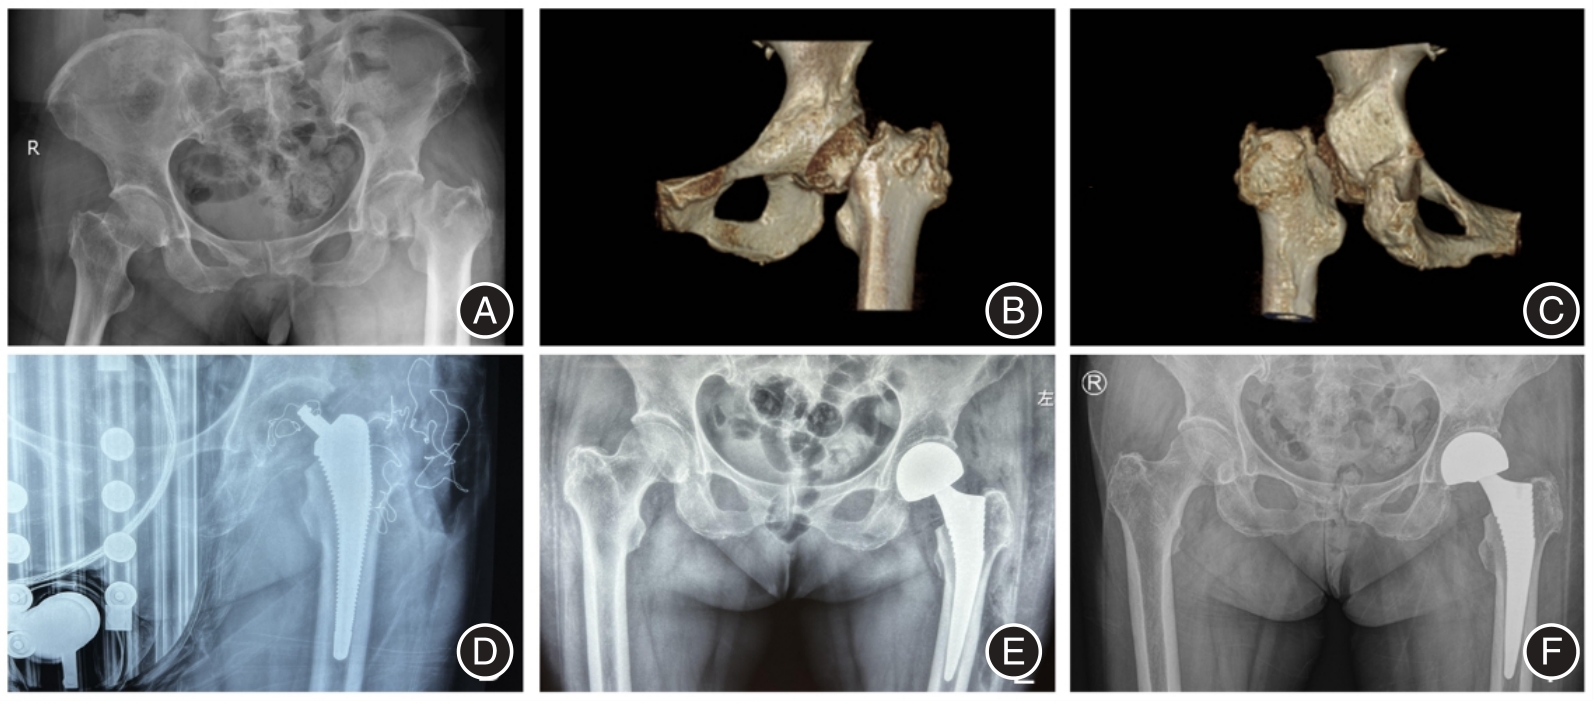

LI Junran, ZHAI Jingxiu, LUO Cheng, WANG Lei, XU Ying, HAN Shuo, LIANG Junsheng, LI Ligeng..

Clinical efficacy of total hip arthroplasty vs hemiarthroplasty through the direct anterior approach for elderly patients with femoral neck fractures

[J]. The Journal of Practical Medicine, 2022, 38(20): 2602-2607.